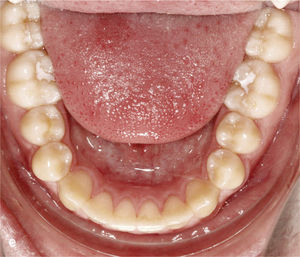

Extracción de dientes anterioresLa falta grave de espacio en el sector anterior hace que en algunos casos sea necesario extraer un diente anterior con el fin de disponer del espacio suficiente para conformar la arcada dentaria y lograr una sobremordida funcional. En la figura 12a se observa la mandíbula de un paciente con falta de espacio en el sector anterior, dientes anteriores rotados y el diente 43 inclinado hacia vestibular. En extracciones realizadas en el sector anteroinferior se colocan sistemáticamente ataches de anclaje en los dientes adyacentes al futuro espacio de extracción. En este caso se colocaron ataches en los dientes 33, 32 y 44, dado que no sólo se cerró el espacio edéntulo, sino que también se realizó una intrusión del sector anteroinferior. La figura 12b muestra el resultado del tratamiento después de la extracción del diente 42 y del cierre del espacio.

Sector anterior de la arcada inferior con dientes rotados y apiñados (a). La conformación de la arcada se realiza mediante la extracción del diente 42 y la colocación de ataches en los dientes 33 a 44. Vista intraoral de la arcada inferior con un aspecto armonioso y el espacio cerrado (b).